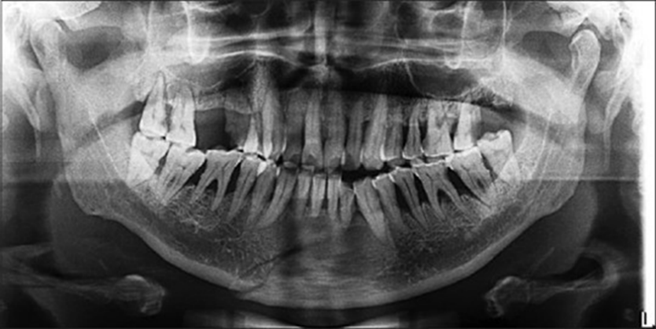

For all the patients who were considered for surgical intervention, the retromandibular approach was chosen. Condylar fracture reduction was done with the teeth in occlusion, and fixation was done with the use of suitable titanium miniplates and screws. Patients were systematically followed up similarly at an interval of day 1, day 3, and weeks 1, 2, 4, and 6 postoperatively [Figures 8-14].

Figure 8: Preoperative orthopantomography